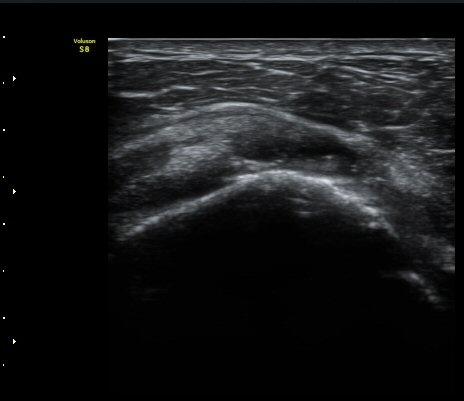

¿À±¸µ¹±â Ⱦ´Ü¸é°Ë»ç»ó ¿Áµ¹±â ¾Æ·¡, ³»Ãø, °ß°©ÇÏ±Ù°Ç Ç¥Ãþ¿¡¼­ ¼ö¾×Àú·ù°¡ °üÂûµÈ´Ù

(±×¸² 3, 4).